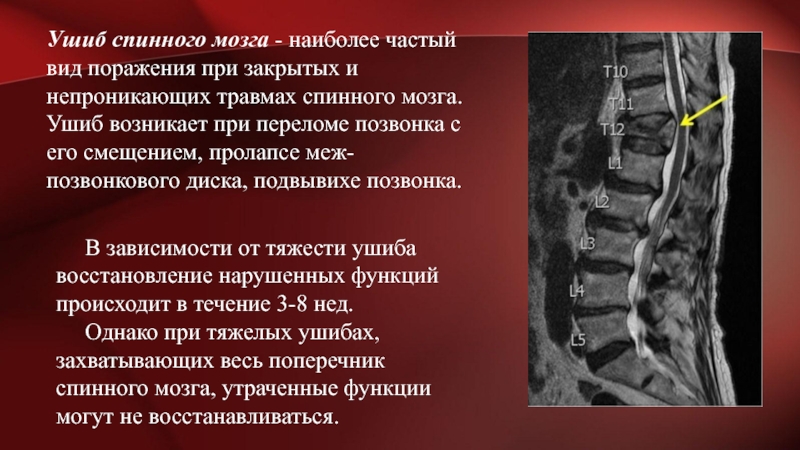

Мрт картина дегенеративно дистрофических изменений пояснично крестцового отдела позвоночника